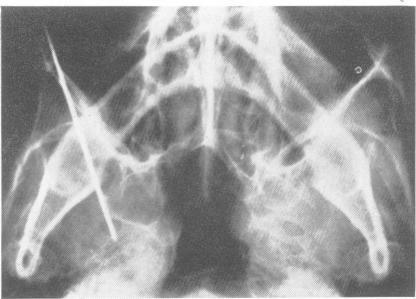

TRIGEMINAL ROOT AND GANGLION INJECTIONS USING PHENOL IN GLYCERINE FOR THE RELIEF OF TRIGEMINAL NEURALGIA.

J Neurol Neurosurg Psychiatry. 1963 Aug;26(4):345-52. doi: 10.1136/jnnp.26.4.345.